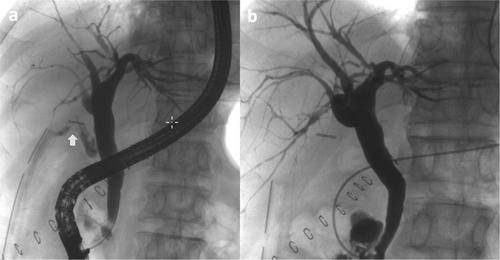

The subjects were 59 patients. The surgical procedures were 31 cholecystectomies, 23 hepatectomies, and five pancreaticoduodenectomies. The severity was Grade A/B/C: 17/40/2. Multivariate logistic regression analysis found that age (unit odds ratio [UOR], 1.09; 95% confidence interval [CI], 1.0–1.19; p = 0.049) and days from surgery to bile leak (UOR, 1.18; 95% CI, 1.04–1.35; p = 0.012) were independent predictors of bile leak severity. Of 40 Grade B biliary leakage patients, 37 patients underwent endoscopic drainage, of which 11 also received intra-abdominal abscess drainage. Eventually, bile leakage was successfully treated in all patients after several endoscopic drainage sessions, and the median drainage period was 18 days (inter-quartile range: 13–35).

In the management of bile leakage after hepatobiliary surgery, elderly patients or patients with late onset of bile leak may be at high risk of severity. Endoscopic biliary drainage is considered a safe and effective treatment for severe patients.